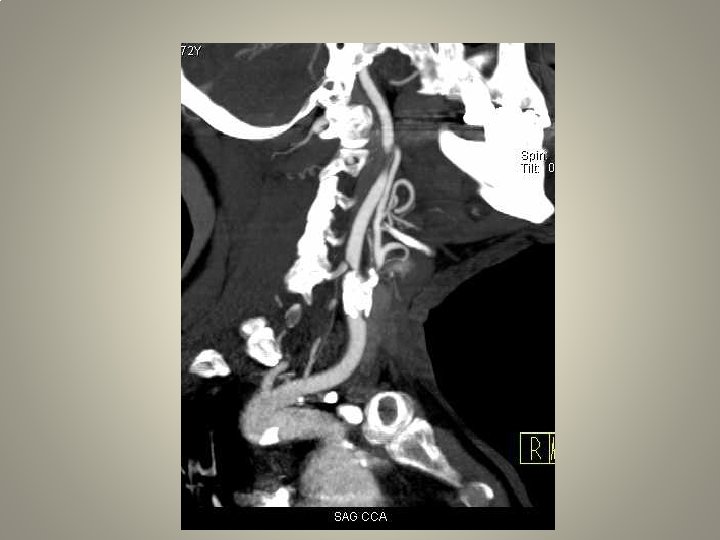

Neden stent? TANDEM lezyon

pre-op • • • Karotis stentleme için uygun hazırlık önemli Anti-agregan kullanımı Hassasiyet ölçümü diffüzyon MR: yeni lezyon? İşlem sırasında sedasyon ağrı duyulmasın Kan basıncı monitorizasyonu

Vasküler erişim • Kateterizasyon: uzun re-inforced sheats (terumo, arrow, cook) uzun diagnostik kateter 120/125 cm Hidrofilik (Terumo 0. 035 -38 stiff or roadrunner-Cook) teller Hidrofilik olmayan (amplatz) teller